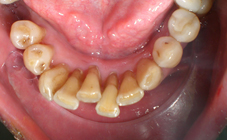

Arcade mandibulaire avant traitement orthodontique, séquelles de maladie parodontale

Après traitement orthodontique et réalisation d’une attelle fibrée (courtoisie Dr Patrick Fournier)